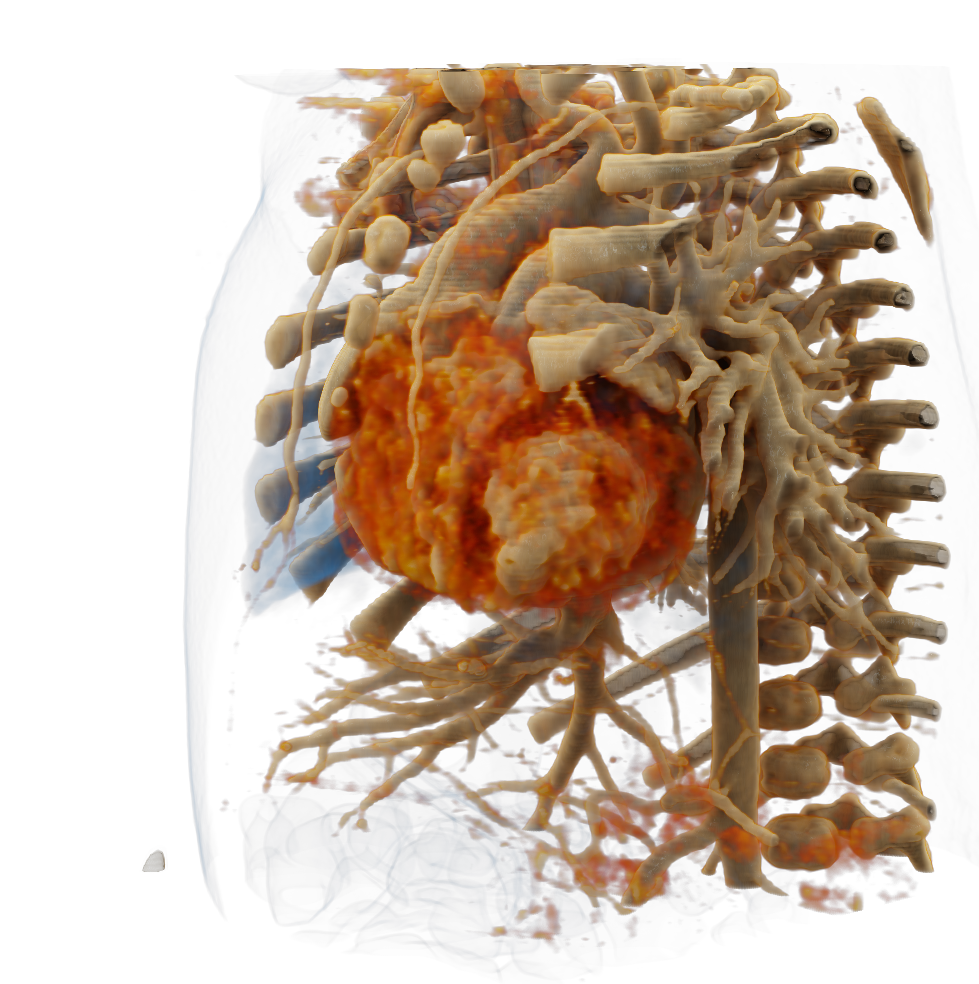

Visualize the smallest structures of the heart realistically without surgery? About the use of a prototype that makes this vision almost tangible.

Cardiac surgery is one of the most difficult procedures, and it gets even more complex when it comes to operating on tiny children’s hearts. Visualization techniques like cinematic rendering provide a detailed 3-D view of the patient’s heart and surrounding anatomy. But what happens when these images are turned into a hologram that can be rotated, zoomed, and looked at from all possible perspectives?